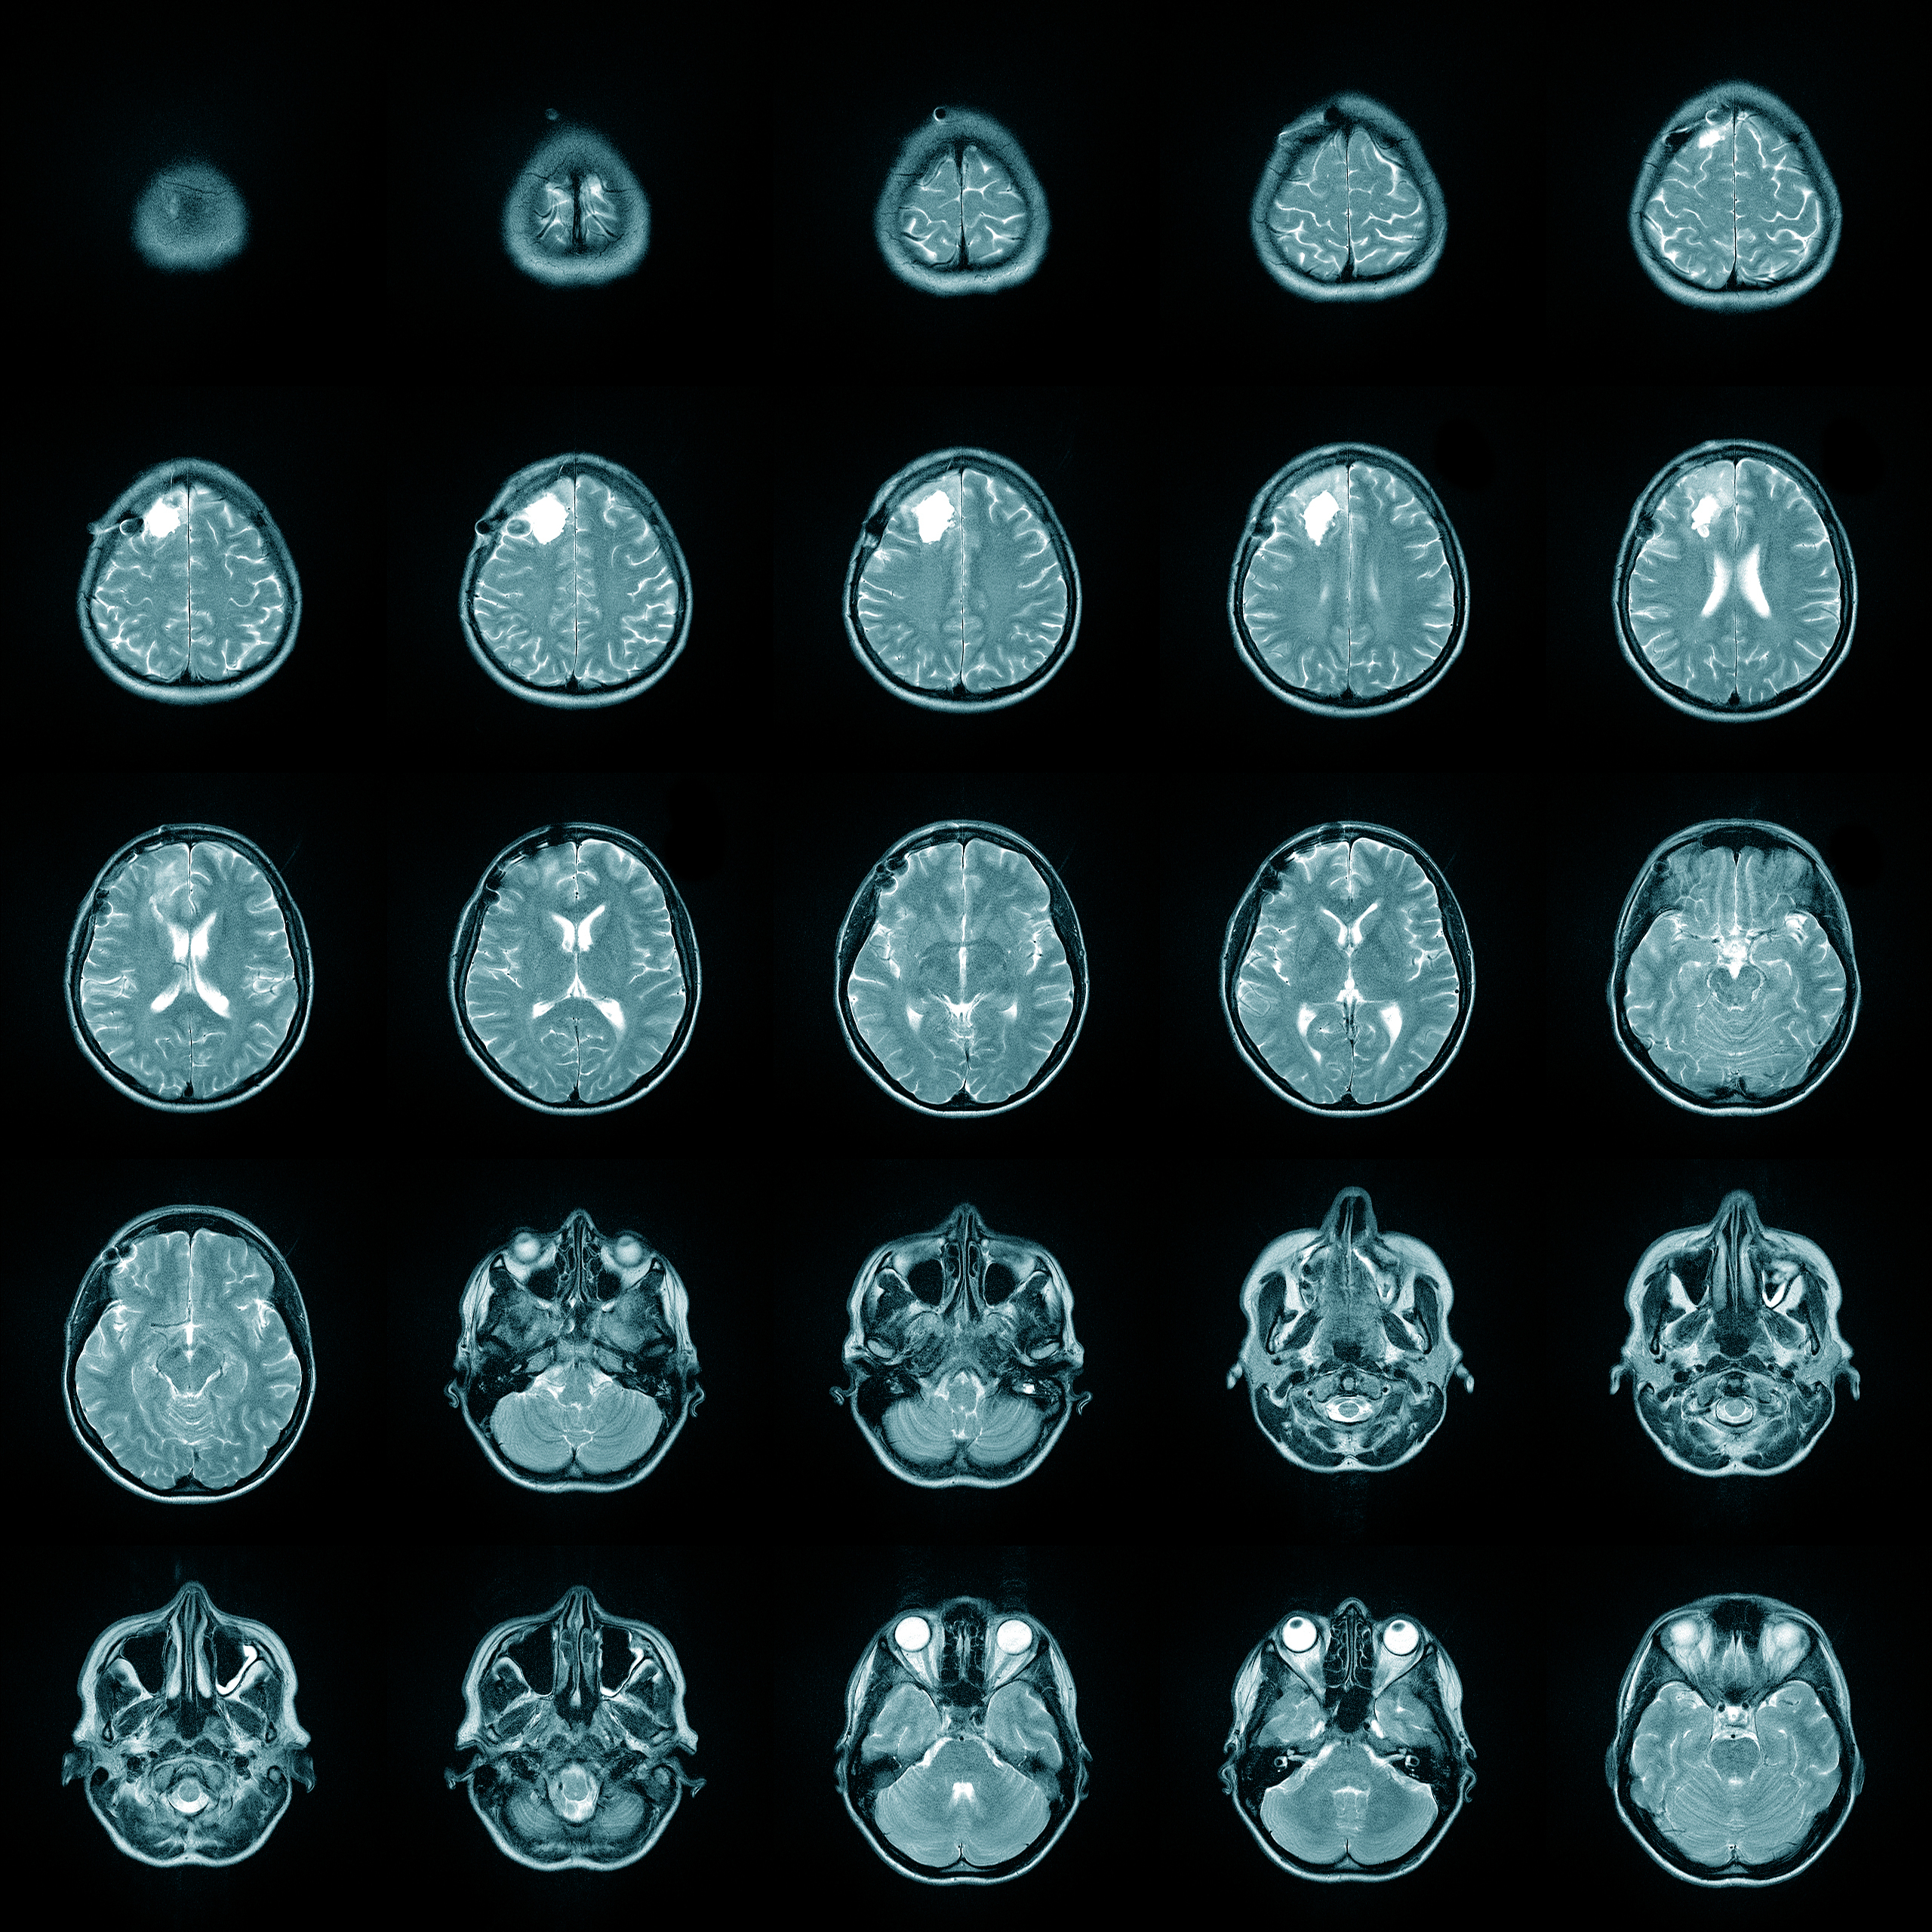

In an outpatient setting, conventional medicine favors brain imaging through functional MRI (fMRI) or single-photon emission computed tomography (SPECT) scans to visualize central nervous system health, while bloodwork is the standard for determining hormone levels. These methods are well-validated for diagnosis, but they have flaws. One problem with using bloodwork to assess hormone levels is that hormones travel bound to proteins when circulating in the bloodstream. Only by extrapolation can active levels of hormone levels be assessed, if at all.